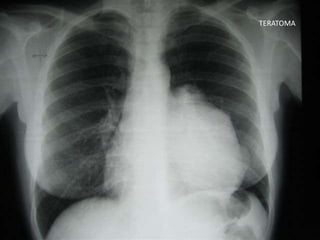

TERATOMA

TERATOMAS

• Ubicación: mediastino anterior

• Edad: sin prevalencias

• Clínica: por efecto de masa

• Variedades: diferenciados e indiferenciados (potencial

maligno)

• Diagnóstico: TAC

– Cápsula con realce del contraste

– Poliloculado

– Contenido líquido o graso

– Calcificaciones

• Tratamiento: cirugía, QTX solo en inmaduros